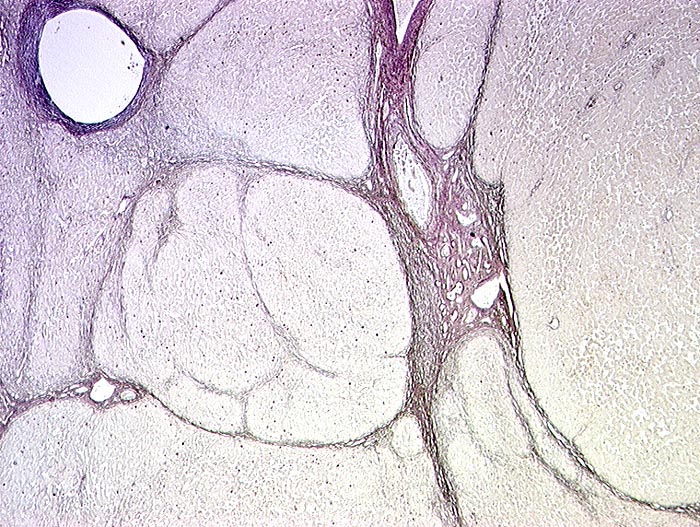

PathoPic ID 1158 - HBs Antigen positive hepatitische Leberzirrhose

HBs Antigen positive hepatitische Leberzirrhose

Entzündung infektiös

Leber

Pseudolobuli ohne Zentralvenen umgeben von Bindegewebe. Kleine braune Punkte in den Pseudolobuli entsprechen Hepatozyten mit HBs Antigen.

Histologie